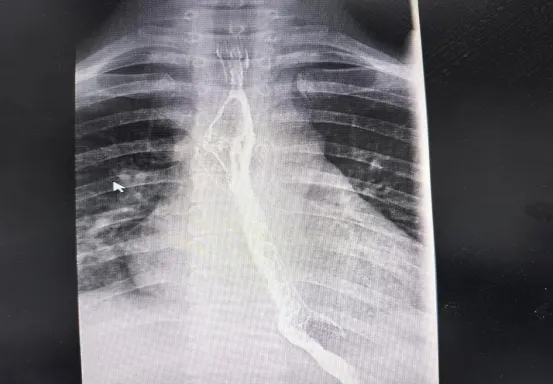

术前食道吞钡显示食管重度狭窄及钡剂潴留

4月16日,由消化内科蔡笃雄主任医师、高飞主治医师,介入血管外科孙刚副主任医师、廖勇主治医师,介入导管室林子义技师、谢春花副主任护师等组成的精锐手术团队严阵以待。内镜下,食管狭窄处仅露出一条细小缝隙,手术难度极高。但在X线透视的精准引导下,手术团队凭借丰富经验和高超技艺,经过多次尝试,终于让导丝成功穿过狭窄段进入胃腔!随后,5mm和8mm扩张球囊逐级撑开狭窄食管,最后顺利置入食道金属支架。造影剂顺利通过食管狭窄段进入胃腔,此次高难度手术取得良好效果。